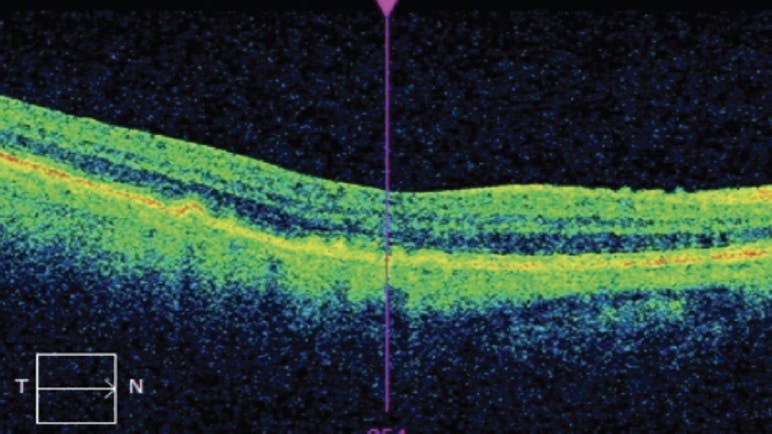

In the case of the patient mentioned at the beginning of this article, OCT imaging was acquired and multiple drusen with irregular RPE were noted (Figure 1). We directed the patient to begin taking AREDS2 vitamins and to return for planned routine eye examinations every 6 months. We referred her to the Notal Vision Monitoring Center (Notal Vision) for home monitoring between in-office visits.